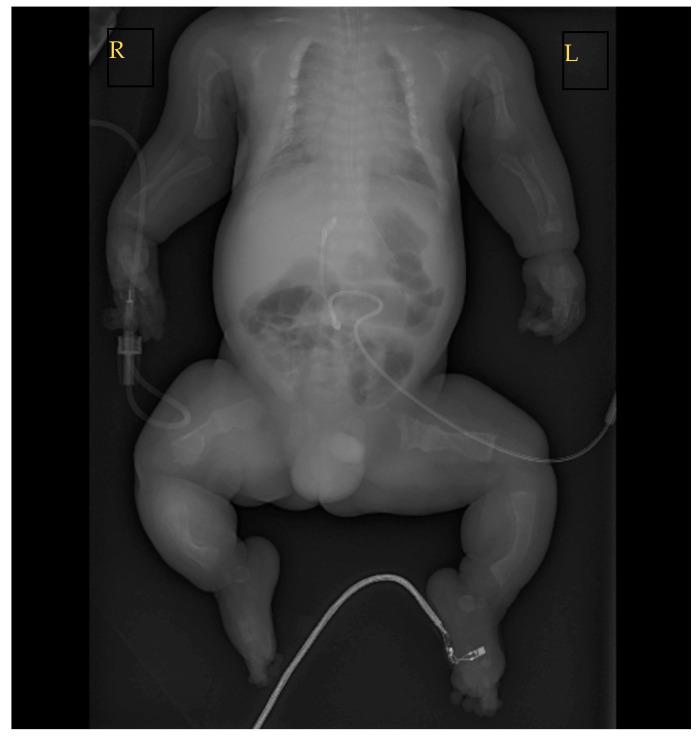

Osteogenesis imperfecta (OI), also known as brittle bone disease, belongs to a rare heterogeneous group of inherited connective tissue disorders. In experienced prenatal centers, severe cases of OI can be suspected before birth from the first trimester prenatal ultrasound screening. In this article, we describe a case report of OI suspected at the 26th week of gestation and the patient's outcomes in infancy one year after birth, as well as compare our case to other prenatally or soon-after-birth suspected and/or diagnosed OI clinical case reports in the literature. This case was managed by a multidisciplinary team. In this clinical case, OI was first suspected when prenatal ultrasound revealed asymmetric intrauterine growth restriction and skeletal dysplasia features. The diagnosis was confirmed after birth using gene variant detection via exome sequencing; the gene variant causes OI types I-IV. The familial history was negative for both pregnancy-related risk factors and genetic diseases. At one year old, the patient's condition remains severe with bisphosphonate therapy.